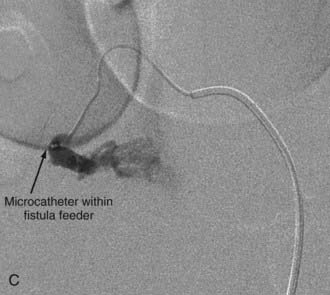

Extradural AVFs are treated almost exclusively by endovascular procedures and only rarely require open surgery.12,22,24 Endovascular treatment usually involves a transarterial approach, but occasionally a transvenous approach provides better access to the fistula.12 Closure of the fistula requires elimination of a small portion of the feeding artery proximal to the fistula, the fistula itself, and a limited portion of the proximal draining vein as well. Some authors advocate the use of fibered detachable coils rather than embolic agents for the treatment of these lesions because there is less risk of the embolic material traveling beyond the target zone with the former material12 (Fig. 396-3).

In type IV-B lesions, the size and flow of the fistula are increased and superselective catheterization is usually possible.10,22 Obliteration of the entire fistula is required; if only the feeder but not the fistula is embolized, the fistula will recruit collateral supply later. NBCA is the embolic agent of choice if the microcatheter can achieve a wedged-flow position.13 The fistula may be closed with coils. Embolization with PVA particles may facilitate subsequent surgical resection or stabilize the neurological deficits (Fig. 396-5).22